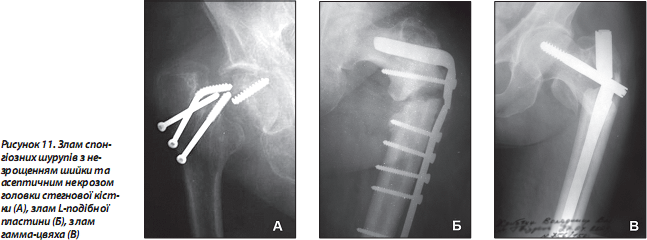

У процесі реабілітаційного лікування можливі злам (рис. 11) та міграція конструкції, вторинні зміщення фрагментів. Ці ускладнення потребують проведення неодноразових органозберігаючих оперативних втручань [20] або адекватної заміни суглоба на штучний [21].